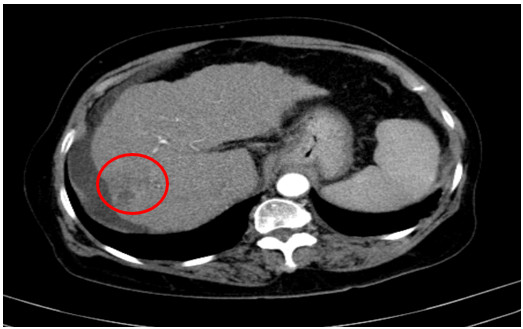

Chụp cắt lớp vi tính ổ bụng

Gan: biến đổi hình thái, phì đại HPT I, bờ gan không đều. Nhu mô gan phải có tổn thương giảm tỉ trọng kích thước 32x34mm, ranh giới không rõ, co kéo bao gan lân cận, trong có phần tăng tỉ trọng của vật liệu nút mạch, không ngấm thuốc sau tiêm

=>U gan hiện tại không còn phần ngấm thuốc trên phim (Vòng tròn đỏ)